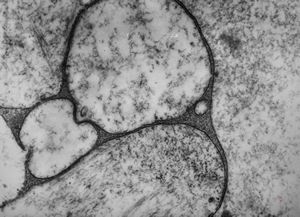

M, 1y. | gangliosidosis … bone marrow